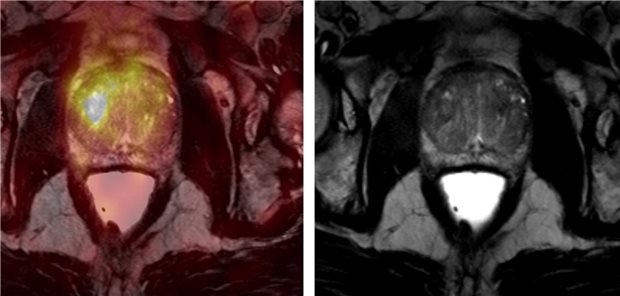

Ein 27 Jahre alter Mann kommt mit akuten Hodenschmerzen in die Ambulanz. Die Ärzte vermuten eine Hodentorsion – entdecken aber einen segmentalen Hodeninfarkt.